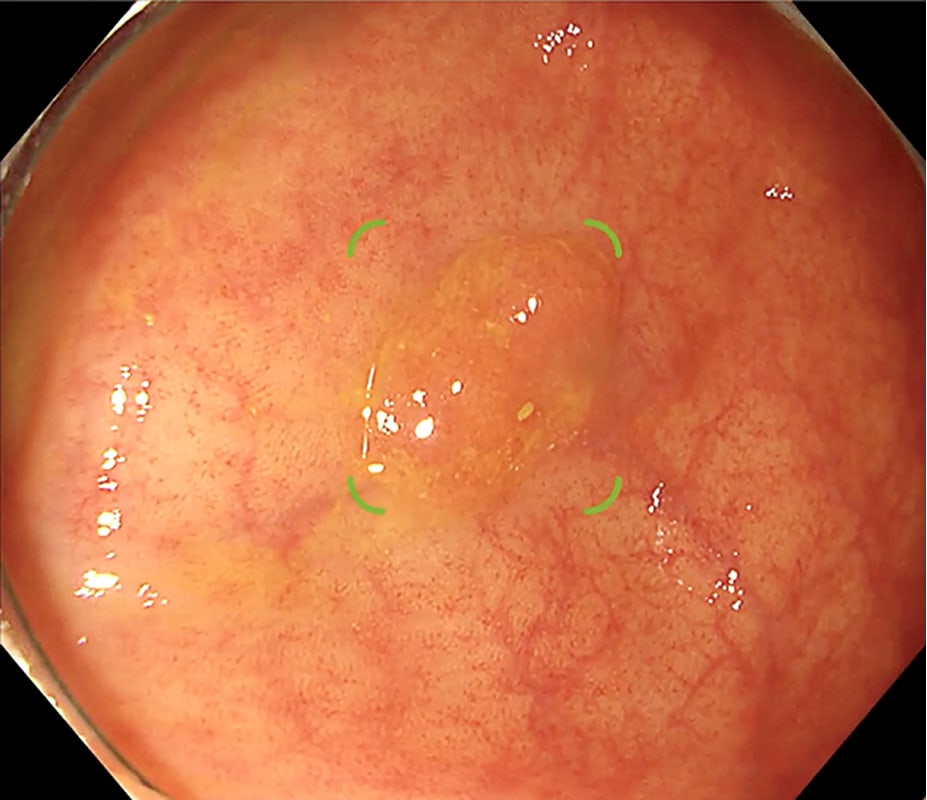

Diagnostic support for detecting brain aneurysms from brain MRA

Brain aneurysm detection support technology advanced from MRA

EIRL Aneurysm supports the interpretation process by identifying sac-like structures of aneurysms in brain MRA that are larger than 2 mm. The sensitivity of the doctor interpreting the images without the software was 68.2%. In comparison, the sensitivity with the assistance of the software was 77.2%, suggesting an improvement in diagnostic accuracy.